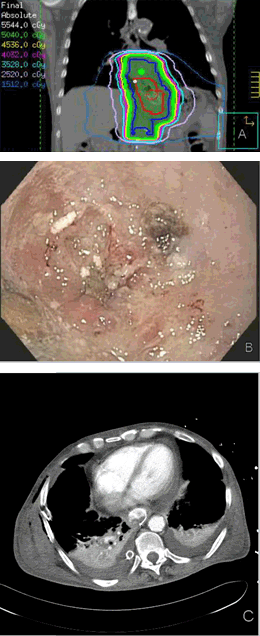

A 68-year-old Caucasian male presented with a three-month history of moderate to severe dysphagia. He did not have any clinical or laboratory evidence of malnutrition. Upper endoscopy with biopsies identified moderately differentiated invasive adenocarcinoma of the distal esophagus, extending to but not past the gastroesophageal junction (GEJ), from 37 to 40 cm from the upper incisors. The tumor was described by the endoscopist to be partially obstructive. By endoscopic ultrasound, American Joint Commission on Cancer clinical stage IIIA (uT3, uN1, M0) was assigned. Computed tomography of the chest, abdomen and pelvis with and without intravenous contrast and positron emission tomography did not reveal any evidence of further locoregional cancer extent or distant metastases. A fully covered SEMS, 18x100 mm in size, was then inserted across GEJ, and this intervention completely relieved his dysphagia. Esophagectomy following neoadjuvant concurrent chemoradiation was recommended by the multidisciplinary care team. The patient, therefore, received 50.4 Gy/28 fractions of external beam radiotherapy along with weekly paclitaxel and carboplatin chemotherapy without interruption or any self-reported discomfort. Unexpectedly, on day-15 from the completion of radiotherapy, he was admitted to the hospital in critically ill condition with a massive, rapidly developed right pleural effusion. Emergent upper endoscopy revealed the esophageal stent to be in a proper position. Incidentally, free flow of liquid was noted trough GEJ, which was covered by the stent. Urgent esophagectomy was deemed not to be feasible. The patient ultimately expired in the intensive care unit on the day-11 of the hospital stay. The most likely cause of death was determined to be esophageal perforation in the region of the endoluminal stent, although severe aspiration pneumonia as the culprit could not be excluded (Figure 1).

Figure 1: Endoscopic and radiographic images in Case 1. (A) Diagram of body region receiving radiotherapy, (B) View of the distal esophageal tumor just prior to stent insertion, (C) Single axial slice of contrast enhanced computed tomography of the thorax, taken on day-3 of the terminal episode showing small bilateral pleural effusions after right chest tube placement.